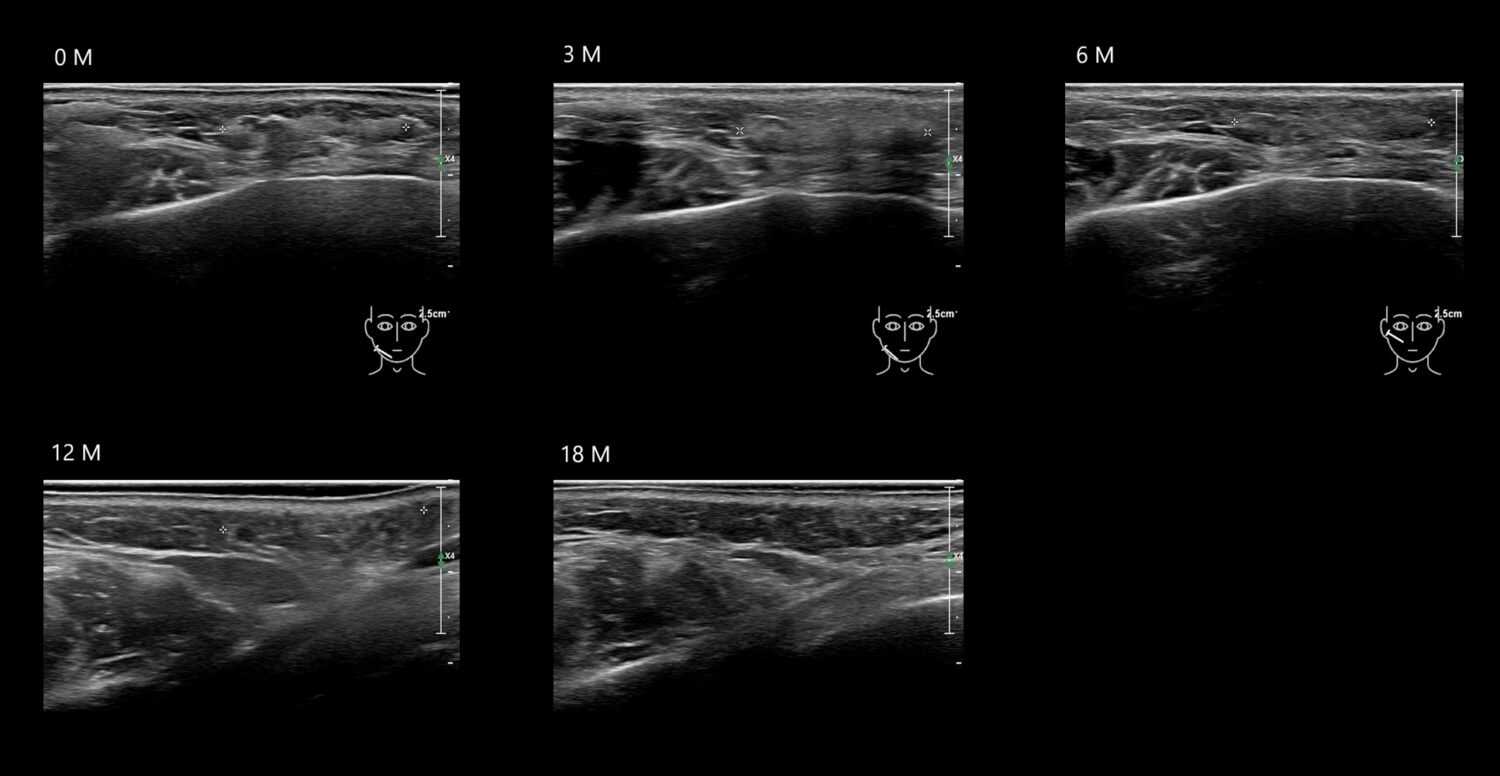

Filler library